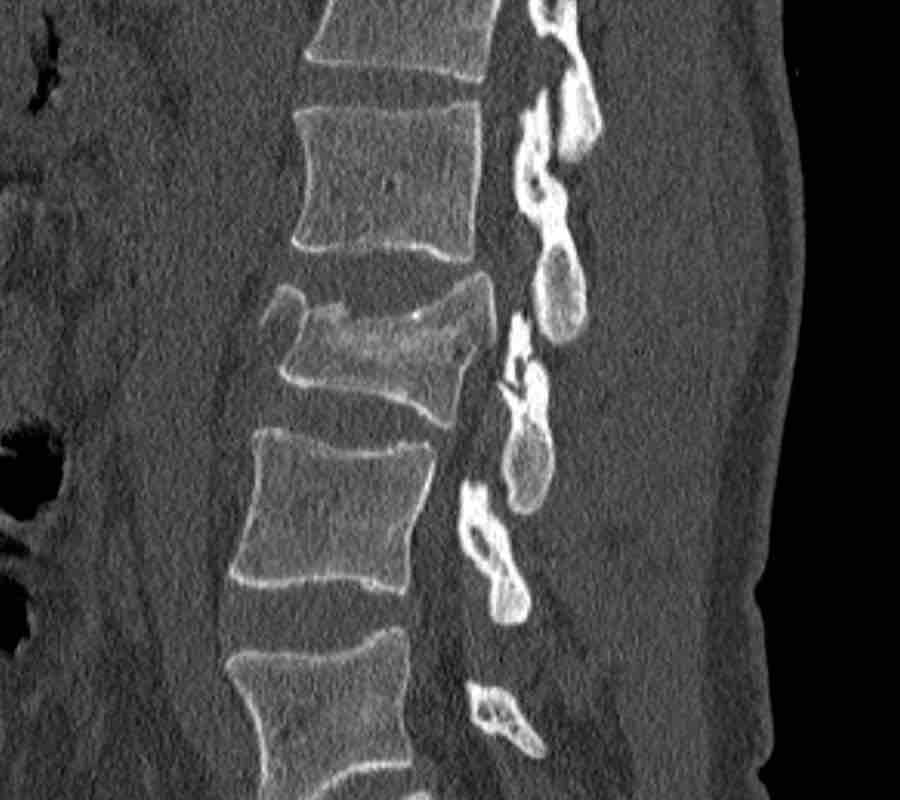

What is the AO-type of the vertebral body fracture based on only these two inages?

Findings:

- Fractures of the vertebral body with involvement of upper endplates (1 points) and posterior wall (2 points)

- Bulging of the posterior wall without any other signs of dislocation is the result of the burst fracture.

Therefore no C injury.

Conclusion

Injury type A3